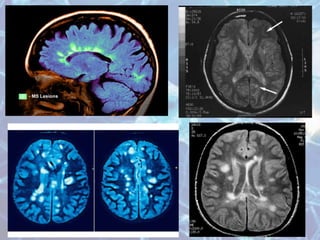

• MRI of the brain is the most accurate test to

diagnose MS, reaching a sensitivity of 85 to 95%

in symptomatic persons.

• Increased T2 and decreased T1 intensity

represent the increased water content of

demyelinated plaques in the cerebrum and spine.

• Enhancement of lesions with gadolinuim

indicates active MS lesions that may enhance for

up to 2 to 6 weeks after an exacerbation.